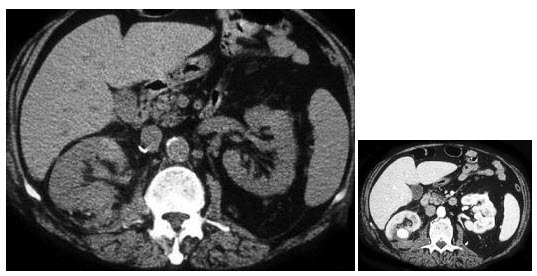

16、多项选择题

男,65岁,左侧腰背部胀痛伴无痛性全程血尿3月余,CT平扫及增强检查如图所示,下列说法正确的是()

A.平扫时见左肾上极有一软组织肿块影,其边界较清楚

B.增强扫描肾皮质期可见肿块明显强化,其内亦有无强化区

C.增强扫描肾实质期可见肿块强化迅速下降,但密度比平扫时仍要高

D.考虑为左侧肾癌

E.考虑为左侧肾错构瘤

点击查看答案

本题答案:微信扫下方二维码即可打包下载完整带答案解析版《★放射医学(医学高级)》或《放射医学(医学高级):CT》题库